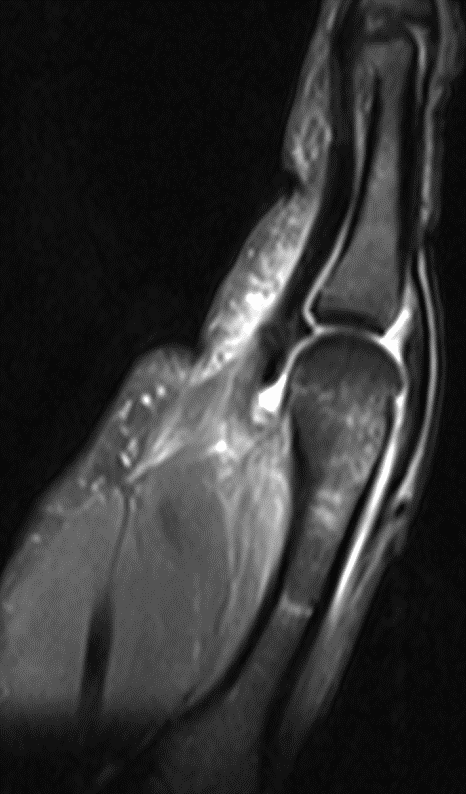

Способ проиллюстрирован чертежами, поясняющими сущность и эффективность заявляемого способа. На фиг.1 - оперативный доступ к сухожилию длинной малоберцовой мышцы в области наружной лодыжки; на фиг.2 - чрезоперативный доступ, теновыделителем проксимально отсекают сухожилие длинной малоберцовой мышцы от мышечного брюшка и выводят сухожилие в область операционной раны; на фиг.3 - отсеченное сухожилие длинной малоберцовой мышцы на препаровочном столике; на фиг.4 - схематично представлено направление проведения каналов, сухожилия и его крепление интерферентными шурупами в мыщелках большеберцовой и бедренной костях, трансоссальная фиксация в головке малоберцовой кости;

на фиг.5 - рентгенограмма коленного сустава в прямой и боковой проекции больного с начальными признаками остеоартроза; на фиг.6 - магнитно-резонансная томография коленного сустава больного, где отсутствует передняя крестообразная связка и наружная боковая связка; на фиг.7 - магнитно-резонансная томография коленного сустава больного, где показана восстановленная передняя крестообразная связка и наружная боковая связка; на фиг.8 - полное сгибание коленного сустава через три месяца после операции; на фиг.9 - стабильность коленного сустава через три месяца после операции.

На МРТ левого коленного сустава до операции в боковой и фронтальной проекциях - отсутствие ПКС и дефект НБС (Фиг.6).

На МРТ левого коленного сустава после операции в боковой и фронтальной проекциях: 10 - пластическое восстановление ПКС дупликатурой сухожилия длинной малоберцовой мышцы, 11 - пластическое восстановление малоберцовой коллатеральной связки сухожилием длинной малоберцовой мышцы, 12 - интерферентные шурупы (Фиг.7).